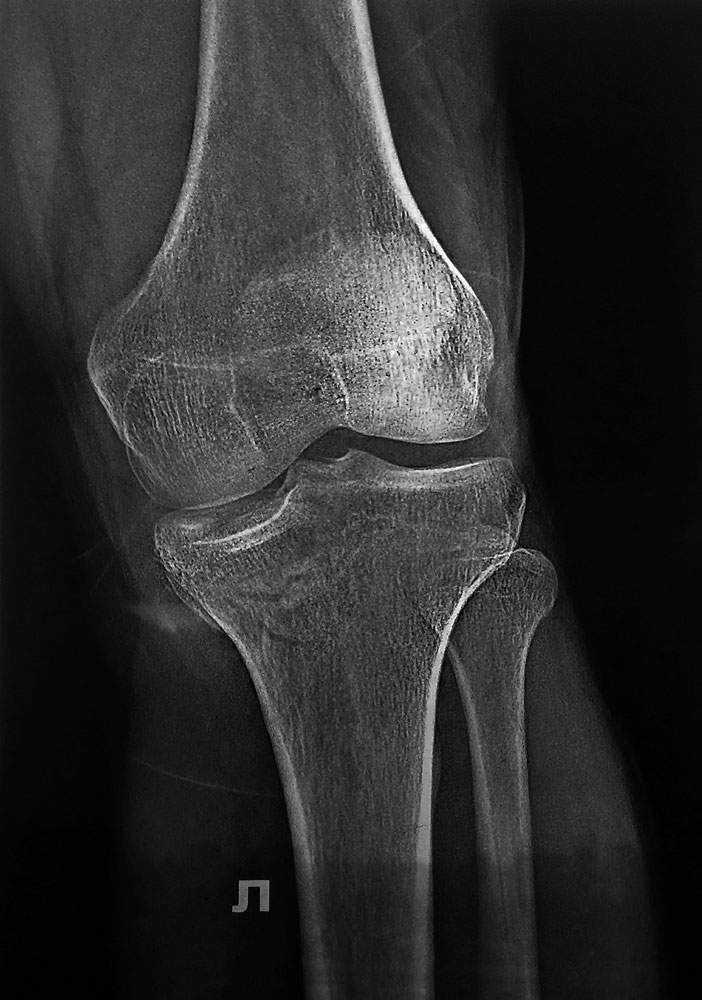

Мужчина, 36 лет, импрессионный перелом медиального (внутреннего) мыщелка ББК левой ноги.

С его слов обстоятельства травмы: Прыгнул с высоты около 3м и при приземлении подвернул ногу.

Прилагаю снимки ренген + КТ Подскажите пожалуйста, какой фиксатор подойдет для данного перелома.